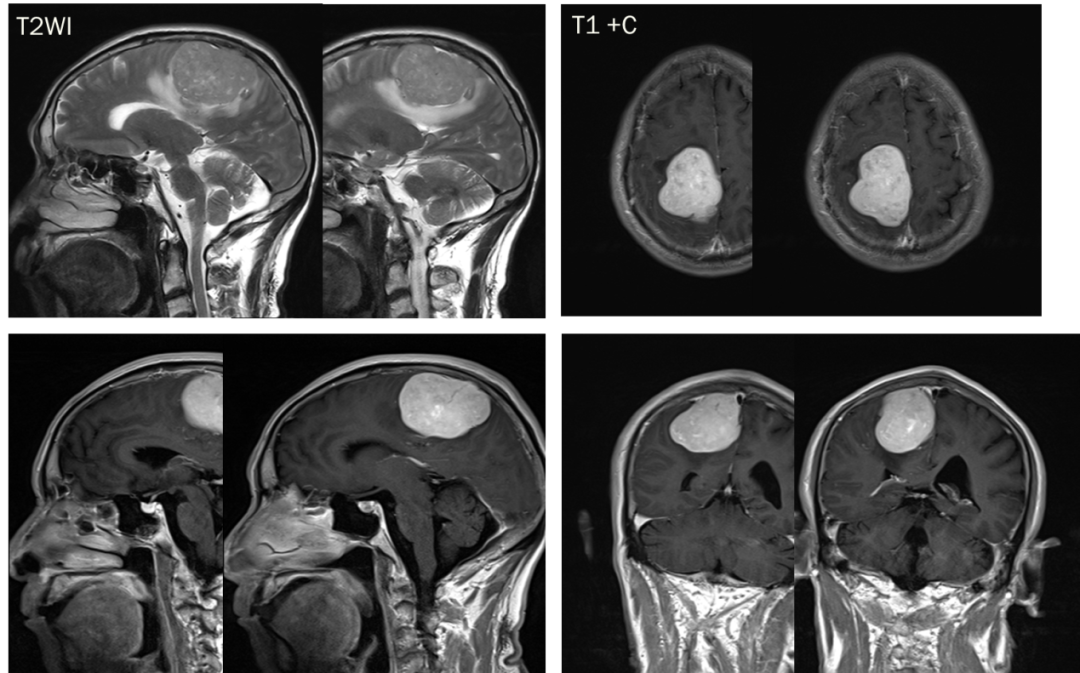

CASE 4

男,62 岁

右侧顶叶区混杂信号占位,T1、T2 内部条样低信号影,血管留空信号;增强可见明显强化,内部信号欠均匀,内见强化迂曲血管影。

诊断:右侧顶叶区血管外皮瘤

影像特征:

平扫:T1WI 及 T2WI 呈等、稍低信号,病灶内可见斑片灶性坏死区,部分病灶内可见流空血管影;肿瘤边界清楚,多数与脑膜相连或与脑膜关系密切,部分病灶周边可见轻度水肿

DWI:呈稍低信号,反应肿瘤血供丰富、生长较快、质地柔软的组织学特点

增强:病灶明显均匀或不均匀强化,病灶内流空血管影可见明显强化,少数病灶可见「脑膜尾「征及瘤周可见供血血管影